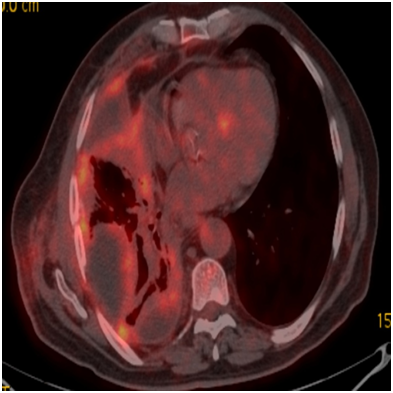

A seventy-five year old male patient referred to our clinic for dyspnea and involuntary weight loss. He was an active smoker for one hundred thirty packets/year, he had not asbestos exposure. Patient was hospitalized to our clinic for pleural effusion and infection six months ago and no malignancy was detected in Thoracic CT and fluid cytology. The patient whom fluid was lowered with ant biotherapy was discharged at the end of the treatment so as to come to the control. Massive effusion was determined in the left hemithorax in the patient who reapplied on the increase of symptoms. Irregular FDG uptake was present in the areas of common linear nodular thickening in the left hemi thorax pleura on PET/CT (SUV max 7.2-11) (Figure 5). Tumor cells composed of invasive glandular structures in the pleura and with mucinous material in cytoplasm were detected as a result of VATS. The tumor is negative in the pleural fluid. CK8/18, CD15, CEA, CK7 was positive and D2-40, calretinin; WT-1, TTF-1 and CK-20 were negative in immunohistochemical staining (Figure 6). Chemotherapy was started to the patient who was diagnosed with invasive mucinous adenocarcinoma.

Figure 5 Irregular FDG uptake (SUV max 7.2-11)in the areas of common linear nodular thickening in the left hemithorax pleura.